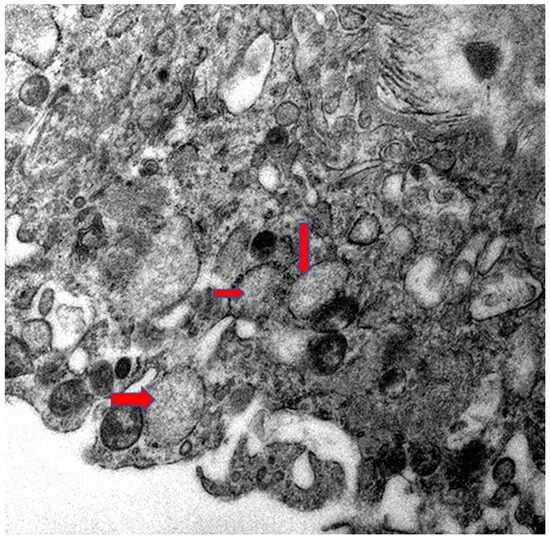

Placental Autophagy Modulation and Ultrastructural Changes in COVID-19 Patients: A Pilot Study Using Immunohistochemistry and Transmission Electron Microscopy

Background: Autophagy is a conserved intracellular degradation pathway essential for maintaining cellular homeostasis by recycling damaged organelles and proteins. Dysregulation of autophagy has been implicated in pregnancy-related complications such as preeclampsia and fetal growth restriction, underscoring its importance in maternal and fetal health. However, the autophagy status in the placental tissue of COVID-19-infected pregnant women remains unknown. Objective: To investigate autophagy activity in term placentas from pregnant women infected with COVID-19 compared to those from uninfected control pregnant women. Methods: In this prospective cross-sectional single-center study, 15 COVID-19-positive and 15 COVID-19-negative term pregnant women who delivered at Sultan Qaboos University Hospital between January 2020 and December 2022 were included. Immediately after delivery, the placental tissue samples were collected and assessed for autophagy activity using immunohistochemistry for LC3B and p62 markers, histopathological examination, and transmission electron microscopy. The proportion and intensity of LC3B and p62 staining were quantified. Statistical analysis was performed using the Mann–Whitney U test. Results: There was a significant reduction in p62 and LC3B expression in both the proportion and intensity in COVID-19 placentas compared to the control group. The proportion of p62 (p = 0.001) and LC3B (U = 46.000, p = 0.003) was significantly reduced in infected placentas. Similarly, intensity levels of both markers showed significant differences (p < 0.05), supporting the evidence of reduced LC3B/p62, suggesting autophagy modulation in COVID-19 patients’ placentas. Additionally, abnormal ultrastructural changes were observed in COVID-19–positive placentas, including mitochondrial injury, endoplasmic reticulum stress, microvillus loss, and basement membrane thickening. Conclusion: The study results from a limited sample size demonstrate a significantly altered autophagy flux in the placental tissues of term pregnant women with COVID-19 infection. These findings highlight the potential impact of COVID-19 infection on placental function and fetal development and underscore the need for further investigation into autophagy-modulating strategies to improve maternal–fetal health. Full article